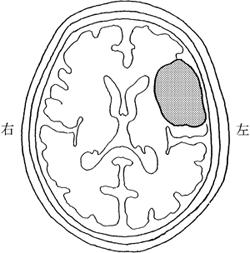

突然の左不全片麻痺を呈して搬送された患者の発症後3時間の頭部MRIの拡散強調像を示す。最も考えられるのはどれか。

1

脳出血

2

脳梗塞

3

脳腫瘍

4

脳動静脈瘻

5

くも膜下出血